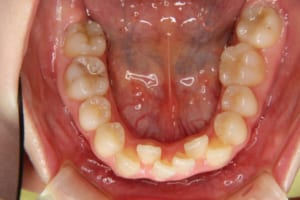

治療前

主訴 下の歯の凸凹

上の前歯が出ているのが気になる

抜歯および非抜歯 上顎:右側中切歯、右側側切歯、左側第一小臼歯

下顎:両側第一小臼歯